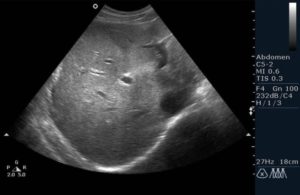

На УЗИ можно видеть такие признаки острого гепатита:

1.Увеличение печени — признак не постоянный и не специфический Не постоянный, потому что вначале заболевания и при легкой степени заболевания увеличения печени может и не быть. А не специфический — потому что печень может быть увеличена при многих заболеваниях, а не только при остром гепатите. При остром гепатите правая доля увеличивается более значительно, чем левая. 2.Диффузное снижение эхогенности печени Говоря простым языком, печень на экране ультразвукового аппарата становится более темной, чем обычно. Такое темное изображение органа объясняется его отеком. Отек — это насыщение органа жидкостью. А жидкость прекрасно проводит ультразвук и практически не отражает его. Поэтому жидкость на экране выглядит темной (не эхогенной или анэхогенной), практически черной. А органы, пропитанные жидкостью (отечные) — более темные, чем нормальные (сниженной эхогенности, гипоэхогенные). О том, что такое эхогенность вы можете прочитать в статье «Что значит эхогенность?» При этом повышается звукопроводимость печеночной ткани. И это понятно: чем больше орган содержит жидкости, тем лучше он проводит ультразвук. Диффузное снижение эхогенности — признак тоже не специфический, так как характерен не только для острого гепатита, но и для некоторых других заболеваний. Например, для застойной печени при хронической сердечной недостаточности. При сердечной недостаточности тоже наблюдается отек многих органов и печени — в том числе. Конечно, опытный доктор ультразвуковой диагностики всегда отличит темную застойную печень от темной воспаленной печени по другим признакам. Но, тем не менее, признак этот не специфичен для острого гепатита. И не постоянен. Так как при легкой степени болезни отек может быть не выраженным и печень останется нормальной эхогенности. 3.Неоднородность ткани печени Этот признак говорит о том, что в ткани печени разные участки подвержены отеку в разной степени. Участки ткани более насыщенные отечной жидкостью выглядят более темными. Участки паренхимы менее насыщенные отечной жидкостью — более светлыми. Признак этот тоже не специфичен и не постоянен. 4.Более выраженный сосудистый рисунок печени Этот признак — тоже следствие отека паренхимы печени. Так как ткань печени становится более темной, на ее фоне более отчетливо видны плотные стенки сосудов. Такой эффект наблюдается только тогда, когда хорошо выражен отек ткани. Он тоже не постоянен и не специфичен. Важно еще и то, что сосудистый рисунок при остром гепатите виден слишком хорошо, но нет деформации и искажения этого рисунка, что бывает при других болезнях печени. 5.При достаточно выраженном отеке слишком хорошо видна капсула печени Изображение капсулы — эхогенное, то есть, светлое, и на фоне темной печени ее видно очень хорошо. Лучше, чем тогда, когда печень имеет обычную эхогенность.